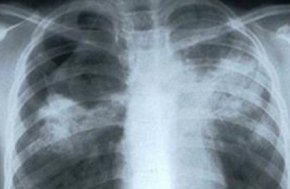

Над 4000 души с рак на белия дроб за 1 г. в България

Всяка година в страната ни се диагностицират 4250 нови случая на рак на белия дроб, като 3260 са сред мъже. Това каза пред журналисти проф. Асен Дудов, председател на Българското онкологично дружество. По думите му тази локализация е водеща причина за смърт от онкологично заболяване в България, предаде бТВ.

Причини за повишаване на случаите на рак на белия дроб са тютюнопушене, излагане на азбест, пасивно пушене, генетична предиспозиция и др.

Повечето случаи на болестта се диагностицират късно - в трети или четвърти стадий, което възпрепятства възможностите за лечение. Късната диагноза е причината за високата смъртност, като 80 на сто от пациентите загиват в рамките на 1 година след диагностицирането.

Целите, които биха могли да ускорят диагностиката и лечението, са повишаване на информираността на населението, намаляване на времето между консултациите и началото на лечението, както и усъвършенстване на програмите за скрининг сред рисковите групи.